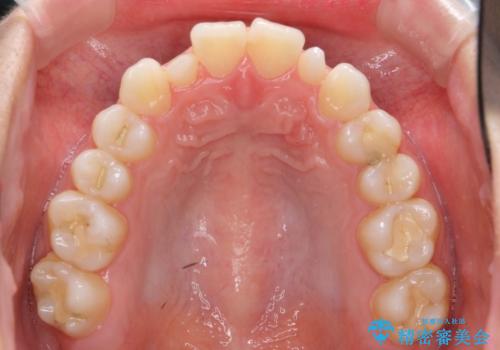

前から2番目の歯が小さく、細くとがった形になっていました。

大きくしようにも、幅が少ない上に、また、内側に入ってしまっているため、矯正治療で前歯を並べてからセラミックでかぶせることにしました。

先に矯正治療をすることで、下の前歯を内側に入れることができ、上の歯のセラミックの幅や厚みを取ることができました。